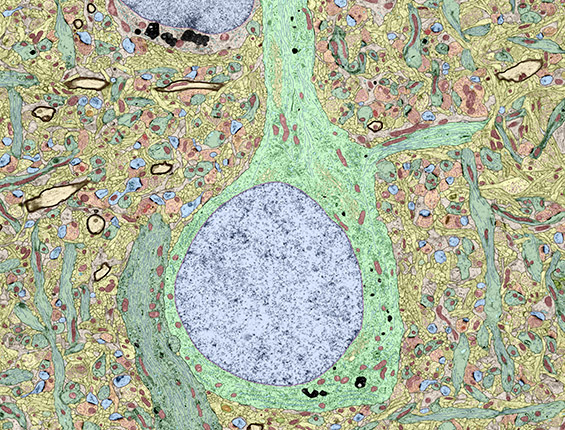

Learning and documenting pathology informatics Designing responsible histopathology workflows

I am Dr. Fernando Soto, a physician and computer science graduate preparing for anatomical pathology residency. Histopath.ai is my public notebook: a living study path, annotated case library, and running project log for the pathology informatics work I build along the way. My current focus is whole-slide imaging pipelines, AI validation, and report-style pathology writing.

Educational case reports emphasising terminology, diagnostic reasoning, and QA follow-ups.

Breast Carcinoma WSI Pipeline

Reproducible workflow for tiling, training, and reporting attention-based slide classifiers on invasive breast carcinoma.

- Standardised patch extraction and stain normalisation using reproducible configs.

- Slide-level attention pooling with integrated attribution overlays for case review.

- Validation dashboards aligned with CAP/CLIA quality metrics and internal QA checks.